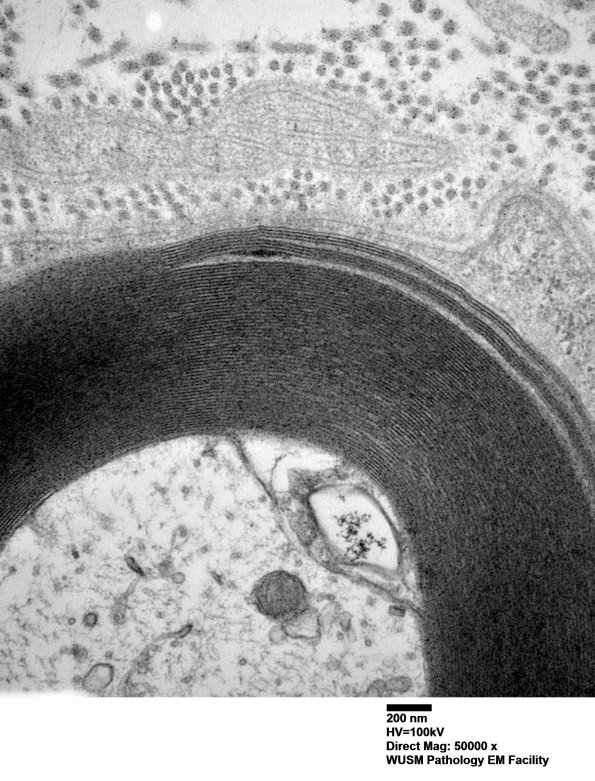

In distinction to the previous case, the number of axons with WSM is limited in extent of involvement of the myelin sheath and only occurs in rare axons. (electron micrographs)